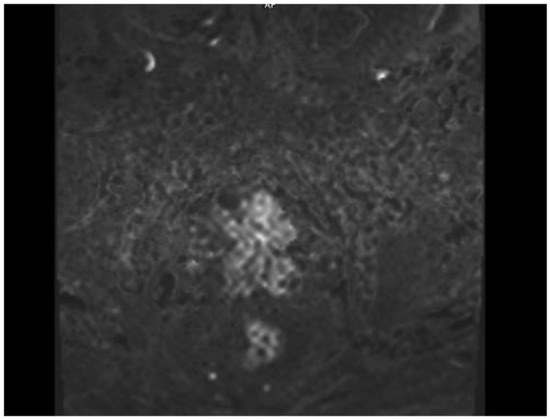

A 77-year-old man presented with several weeks of exertional dyspnea and intermittent dry cough. His past medical history was notable for ankylosing spondylitis, chronic gastritis, a left salivary gland tumor resected 11 years prior (pathologic details unknown), and a cholecystectomy. He had a significant smoking history (20 pack-years) but quit 32 years earlier. An initial chest radiograph, obtained to evaluate possible heart failure, revealed a large right-sided pleural effusion. Figure 1 A contrast-enhanced computed tomography (CT) of the chest further delineated multiple pleural nodules (up to 17 mm) and diffuse, bilateral small pulmonary nodules. Figure 2 and Figure 3 Two thoracenteses drained ~3800 mL of hemorrhagic pleural fluid in total. Fluid cytology was negative for malignancy, and no cell block preparation was performed. Further evaluation with bronchoscopy and bronchoalveolar lavage was unremarkable for infection or malignant cells.

Figure 1. Chest X-ray—right pleural effusion, thickening of the pleura on the right side, bilateral small nodules.